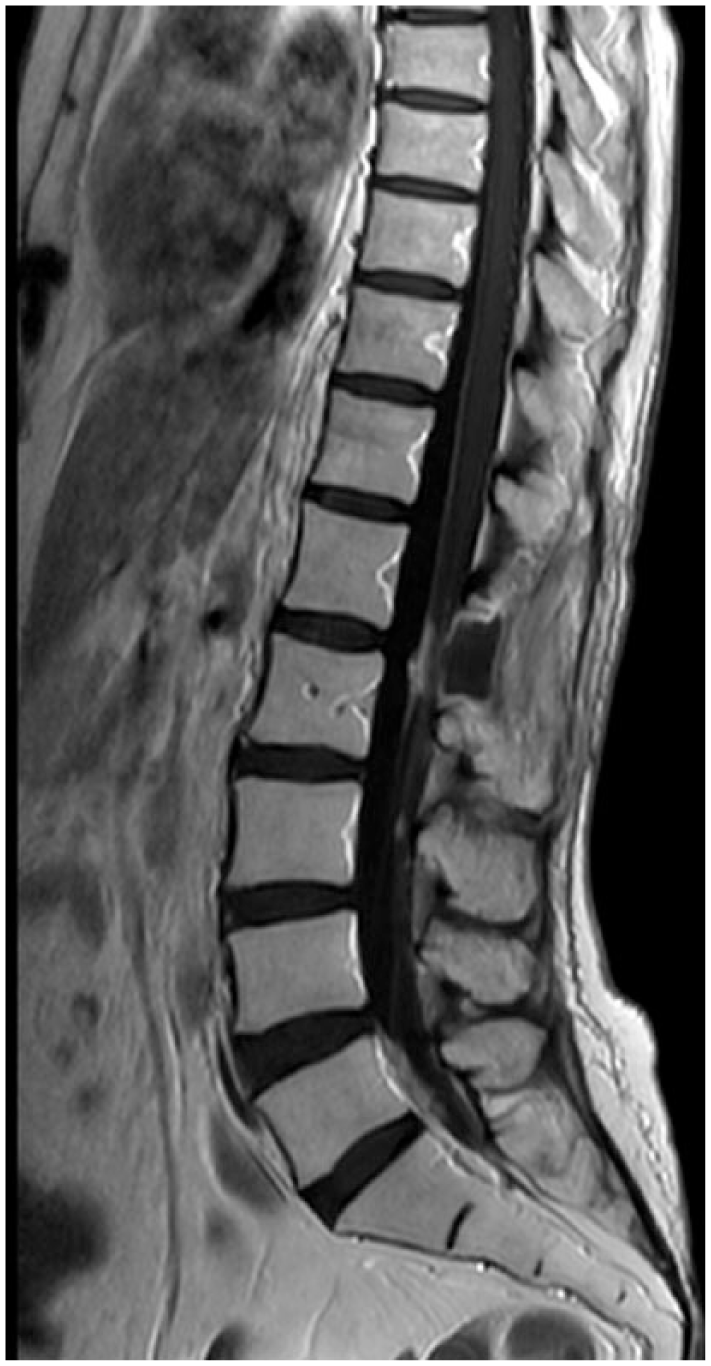

Linear or nodular enhancing lesions of the cranial nerves and spinal nerve roots (e.g. cauda equine), brain sulci and cerebellar foliae are the most common findings32,33 (Figures 1–3). NM lesions typically are small in size (<5 mm) and with complex geometry, thus a quantitative analysis with current MRI technology is difficult. 34 Other neuroimaging techniques (MRI spectroscopy, MRI perfusion, MRI diffusion and positron emission tomography) are not currently employed. Communicating hydrocephalus could be observed in 11–17% of patients, and CSF flow studies, including radioisotope cisternography, are useful in the case of suspected CSF blockage or altered intrathecal drug delivery.35,36

Enhanced lesions in the cauda equine.